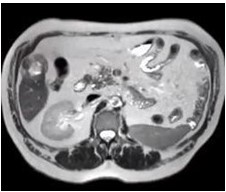

Reportamos el caso de un paciente masculino de 65 años de edad quien consultó por control. Con antecedente de carcinoma de células claras de riñón izquierdo estadio II ameritó nefrectomía radical izquierda y adenocarcinoma de próstata Gleason 9 avanzado oligometastásico, recibió tratamiento con bicalutimada, zoladex y abiraterona acompañado de radioterapia 39 ciclos; hábito OH acentuado, durante la consulta se le evidencia mediante ecografía abdominal lesión ocupante de espacio de segmento V hepático. Fue estudiado con tomografía con protocolo hepático donde se evidencia imagen redondeada de 4,7 cm, que presenta captación discreta heterogénea periférica en fase arterial, lo que sugiere área de necrosis central y un wash out lento en fase de eliminación, dicha lesión está ubicada en el segmento V y se encuentra en íntima relación con los músculos de la pared abdominal anterior ( Figura 1 y 2), Fibroscan en el cual no se evidencia cirrosis hepática, sin embargo, en vista del tamaño del tumor y antecedentes del paciente se decide realizar resonancia magnética nuclear (RMN), en la cual se evidencia lesión redondeada, bien delimitada, heterogénea que mide 5 cm x 4,5 cm x 4,2 cm en lóbulo hepático derecho segmento V con un volumen aproximado de 50 cm3 (Figura 3 y 4), pruebas de funcionalismo hepático alteradas AST 301U/l, ALT 206U/l, alfafetoproteína 244,10 ng/mL, antígeno carcinoembrionario 2,23 ng/mL, Ca 19-9 1,00 U/mL, con CT PET del año anterior negativo, por lo cual se decide realización de intervención quirúrgica con sospecha diagnóstica de carcinoma hepatocelular.